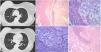

A 52-year-old woman with stage IA infiltrating lobular breast cancer underwent right radical mastectomy with immediate reconstruction. In her oncological follow-up, a cannonball radiological pattern was observed (Fig. 1), so one of the nodules was biopsied for histologic typing.

(A–B) Pre-operative CT image showing bilateral pulmonary nodules. A) Subpleural pulmonary nodule in the anterior segment of the right upper lobe. B) Left lower lobe pulmonary nodules. (C–F) Histologic images of the pulmonary nodule resected during surgery. C) Pulmonary parenchyma and bronchiole observed on the left, and on the right a nodule consisting of cells that appear light-colored at this magnification, with an incomplete lymphocytic rim (a foreign body granuloma variant). D) At higher magnification, these cells are seen to be histiocytic with a large “blank”, i.e. empty cytoplasm, because the silicone dissolves as it is processed, leaving a hollow space. E) Foreign body granuloma in the lung parenchyma near a vein. F) At higher magnification, the typical histiocytes and multinucleated giant cells are seen in more detail.

Atypical right S3 segmentectomy was performed by video-assisted thoracoscopy and, surprisingly, an intra-pulmonary nodule was reported, consisting of intra-cytoplasmic oily material with a lymphocytic rim, with the presence of giant cell microgranulomas with intravascular oily material, consistent with a diagnosis of pulmonary siliconoma (Fig. 1).